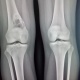

Девочка,2000г.р,делали снимок после травмы правого колена. Вот такая картина справа. Честно сказать в практике не встречалось,только в книгах видела подобные снимки. Верно ли будет мое заключение: фиброзная остеодистрофия.

Фиброзная дисплазия

Она самая.

Я бы уточнил: ГКО. Контроль в динамике.

+ 1 к ФД, ГКО в диафизе - редкость

+1. Многовато всего для простой фиброзной.